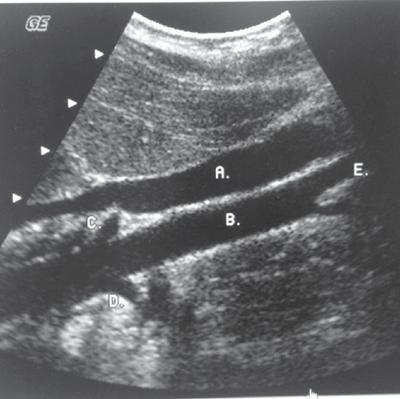

100

What is the letter B?

Aorta

200

What is the long arrow  pointing at?

Hepatic artery

300

What is the red arrow pointing at?

SMA

400

What is the short arrow pointing at?

Splenic Artery

500

What is number 3?

LRV